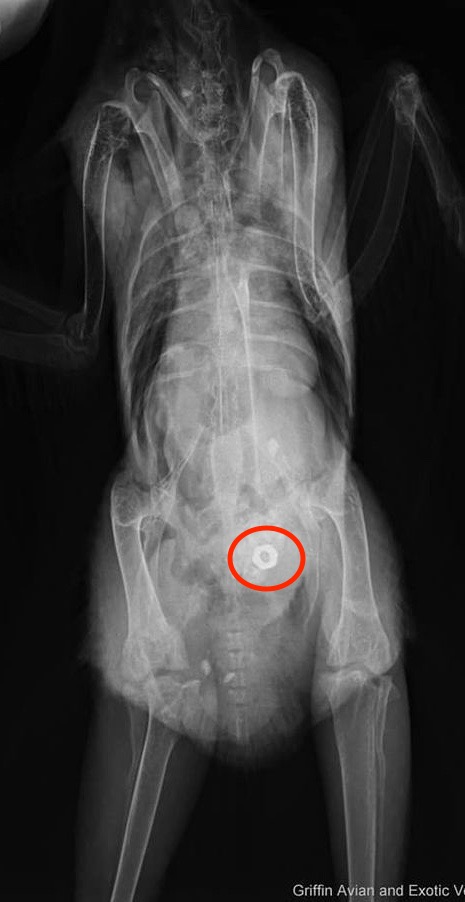

Concerned that one of her birds ate them she took all three chickens to the vet for X-rays to determine who it was. The radiographs revealed that Etta had a hex nut in her gizzard, but the wing nut was still missing. None of the birds showed any signs of illness.Etta was crated so Ashley could monitor if, and when, the nut passed.

Day 5: Etta returned to the vet for a follow up X-ray and the nut had now gone from her gizzard back up into her crop. They wondered if she had attempted to regurgitate it, but the unanimous decision was she passed the nut then, attracted to the sparkle in her poop, promptly ate the nut again.

Day 16: After another week of waiting for the hex nut to pass and not finding it, Etta went back for another x-ray. It was still in her gizzard, but appeared as though she had not reingested it. She was given Lactulose, a chicken laxative, and more fibre in her diet with the hope that it would assist in excreting the nut. The concern was that it could become embedded in her gizzard, possibly requiring a surgical intervention to remove it.

Week 5: After several more days of laxatives and lots of snacks to try to flush out the nut, today’s x-ray revealed not only was it still there, but it appeared that Etta had found something new to eat.

Dental Bur and Hex Nut

Ashley works as a dental assistant and it appears that her work followed her home in the form of a carbide football dental bur, which is a tool that attaches to a hand piece, used to cut and smooth teeth and composite, a tooth-colored material.

The ¾” long bur was a risk for damaging her intestinal tract. If it didn’t pass on its own by the end of the month she was scheduled for surgery. Ashley planned to ask for the return of the ingested bur and hex nut so she could mount and frame them.